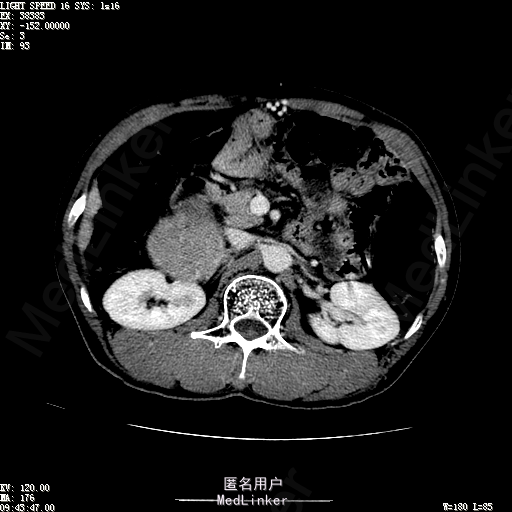

查体:体温36.4℃,脉搏76次/分,呼吸18次/分,血压110/70mmHg。神志清晰,发育正常,营养中等,体位自如,表情安静,慢性病容,检查合作。皮肤粘膜颜色正常,无瘀点、紫癜,有肝掌,无蜘蛛痣,无水肿,毛发的生长与分布正常。浅表淋巴结浅表淋巴结未触及肿大。无巩膜黄染,结膜正常。口唇红润,粘膜正常,舌正常,牙龈正常,扁桃体无肿大,无咽部充血。颈部外形对称,颈静脉正常,肝颈静脉回流征阴性,气管居中。甲状腺正常,无颈部血管杂音。胸部形态正常,呼吸运动平稳规律,无呼吸困难,肋间隙正常。触诊语颤正常,无胸膜摩擦感,肺下界位于右锁骨中线第六肋间。呼吸音正常,未闻及干湿啰音,无胸膜摩擦音。无心前区隆起,心尖搏动正常,心率:76次/分,心律齐,心音正常,无杂音,无心包摩擦音。无大动脉及周围血管征,无奇脉及交替脉,无水冲脉,无枪击音,腹型对称,无腹壁静脉曲张,未见胃肠型及蠕动波,无瘢痕,脐部正常。无压痛,无反跳痛,无腹肌紧张,无腹部包块。肝未触及,Murphy征阴性,脾未触及,肾未触及,无移动性浊音。无肝区叩击痛,无肾区叩击痛,无脾区叩击痛。肠鸣音正常4次/分,无气过水声。外阴及肛门:未查。四肢正常,关节正常,无下肢水肿,无下肢静脉曲张,无杵状指趾。 辅助检查:彩超:肝表面欠光滑,肝内占位5.2*5厘米 ct如下图

诊断:乙肝肝硬化 代偿期 原发性肝癌。 患者病史明确,目前化验转氨酶轻度升高,说明有活动性肝损伤,白蛋白降低提示肝脏合成代谢功能下降,AFP从一年前至今逐渐升高,提示活性肿瘤细胞增多。CT所见明确诊断肝癌,并有周围卫星灶,应近期行TACE治疗。 处置:DSA下肝动脉造影及TACE 手术简要经过:患者平卧位,术区皮肤消毒,铺手术巾,2%利多卡因局麻后,Seldinger法穿刺右股动脉,入血管鞘,5F猪尾管腹主动脉造影,超滑导丝yidao5F RH管腹腔干、肠系膜上动脉、左肾动脉分别造影,腹腔干造影时,见肝右叶7-8处小结节样肿瘤染色,未见外凸生长较大病灶染色。微导管超选肝右动脉注入三氧化二砷碘油混悬液10毫升,横结肠遮挡部位见较大病灶有伞状碘油沉积。复查造影未在见肿瘤染色,拔出导管和血管鞘,穿刺处压迫止血,加压包扎。术毕。

患者术后8天来,无不适,无发热,无腹痛和腹胀,无恶心呕吐,食欲睡眠好,尿便正常。 查体:神志清,巩膜无黄染,心肺听诊无异常,腹软,无压痛,肝脾肋下未触及,移动性浊音阴性,双下肢无浮肿。 复查化验结果:丙氨酸氨基转移酶 116 U/L、天门冬氨酸氨基转移酶 41 U/L、胆碱酯酶 1995 U/L↓、总蛋白 56.3 g/L、白蛋白 25.9 g/L。白细胞计数 5.8 10^9/L、红细胞计数 3.18 10^12/L、血小板计数 175.0 10^9/L、*血红蛋白 83 g/L、血小板分布宽度 15.7 、血小板压积 0.175 %、*红细胞压积 24.6 %、平均红细胞血红蛋白 26.1 pg、平均红细胞血红蛋白浓度 337.0 g/L、平均红细胞体积 77.5 fL、平均血小板体积 10.0 fL、嗜碱性粒细胞百分比 0.4 %、嗜碱性粒细胞数量 0.02 10^9/L、中性粒细胞百分比 70.4 %、中性粒细胞数量 4.10 10^9/L、嗜酸性粒细百分比 2.1 %、嗜酸性粒细胞数量 0.12 10^9/L、单核细胞百分比 12.2 %、单核细胞计数 0.7 10^9/L、淋巴细胞数量百分比 14.9 %、淋巴细胞计数 0.9 10^9/L。甲胎蛋白 23564.00 ng/mL 患者术后第8天开始行FOLFOX6化疗。CT上可见明显碘油沉积,术后甲胎蛋白下降治疗有效。嘱患者术后必须定期复查